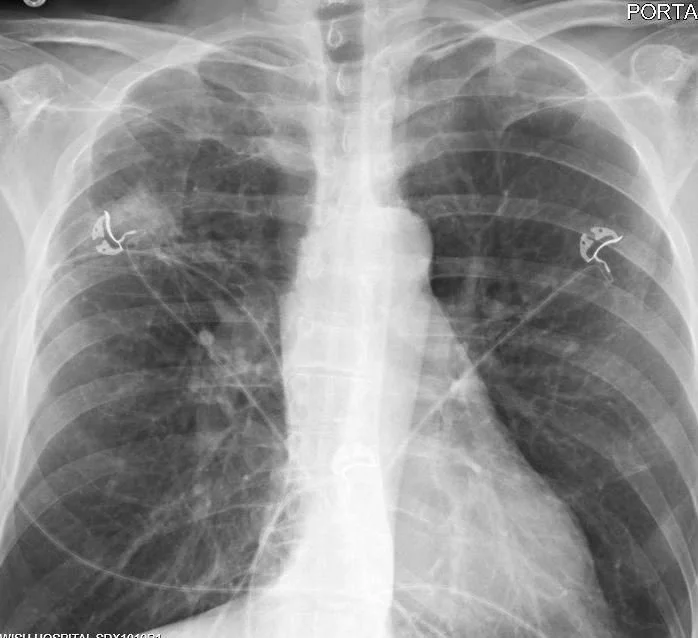

A 54 y.o. male, with a history of lung cancer, comes in with nausea and vomiting. His cxr is shown below.

He is in DKA with no history of diabetes; can you predict what chemo he is taking?